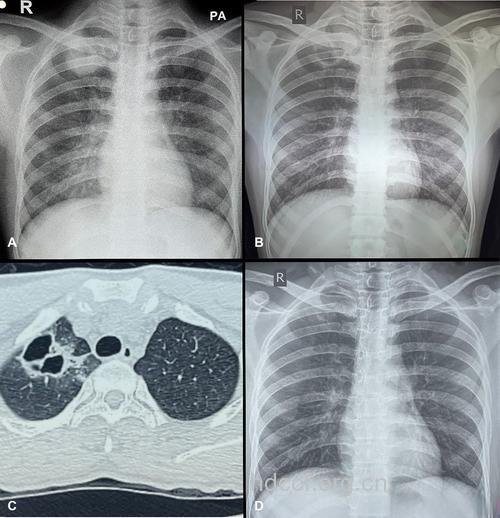

胸部X线表现为粟粒状或模糊阴影,中下肺野、两侧分布为多。经治疗后肺部X线异常可很快消失。但慢性患者常遗留肺间质纤维化。